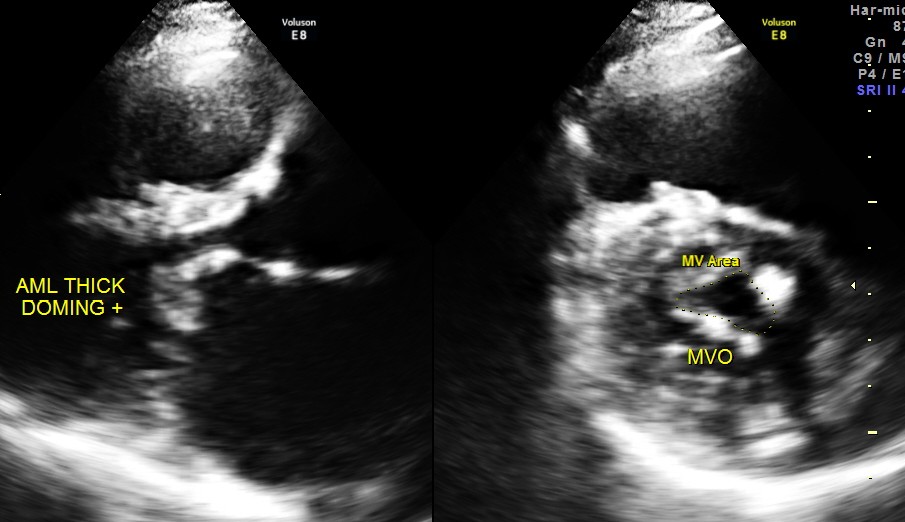

Her Echo cardiogram showed the following findings :

This patient had Rheumatic heart disease , moderate mitral stenosis with pulmonary hypertension .